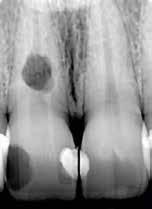

Az elváltozást egy diagnosztikai céllal készített panoráma-röntgenfelvételen észlelték. Az elváltozás kiterjedésének pontos meghatározása, valamint a kezelési terv felállításának és a várható prognózis megítélésének elősegítése érdekében CBCT-felvétel készült (1. a–c ábra). A reszorbtív lézió a fog gyökerének középső harmadában helyezkedett el és a

gyökér meziális felszínét perforálta. A lézió kerek és szimmetrikus volt, amely gyulladásos típusra utalt. Az oszteolitikus terület fókusza a perforáció közelében helyezkedett el (2. ábra). A csontban lévő lézió és a gyökérperforáció az endodonciai kezelés sebészi kiegészítését tette szükségessé. Ennek megfelelően az egy ülésben történő gyökérkezelést követően

1. a–c ábra: Kiindulási CBCT-felvétel. Az axiális síkú metszeten jól látható a gyökér falának perforációja (a); Koronális irányú metszet (b), Saggitális irányú metszet